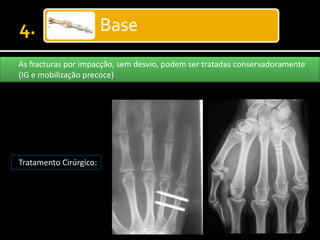

Base

As fracturas por impacção, sem desvio, podem ser tratadas conservadoramente

(IG e mobilização precoce)

Tratamento Cirúrgico:

• #25 Impaction fractures of the metacarpal bases that are not significantly displaced can be treated with splinting, followed by early mobilization.